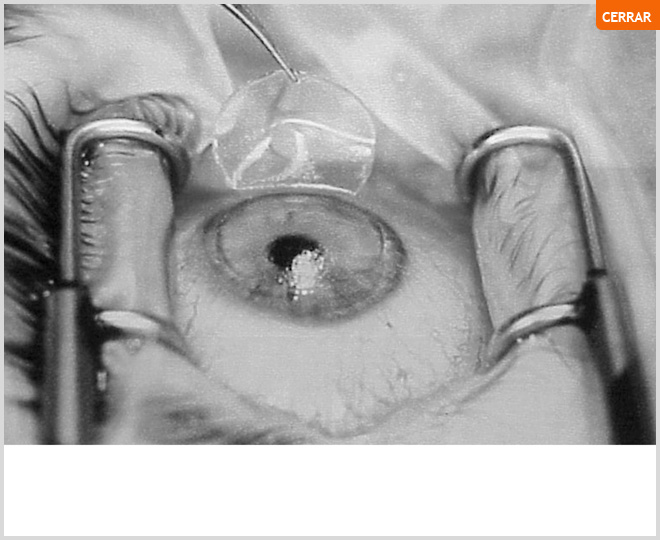

Cirugia de Cataratas. Técnica Ecce.